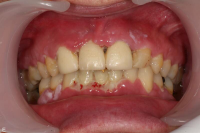

Förekomst av gingivala hyperplasier med djupa tandköttsfickor och svåra hygienförhållanden som följd.

En volymökning av mjukvävnaden kring tänderna som är associerad med intag av läkemedel tillhörande grupperna antiepileptika, immunosuppressiva läkemedel och kalciumblockerare.

Inflammation är den utlösande faktorn som driver tillväxten av mjukvävnaden därför är plackkontroll av största vikt.